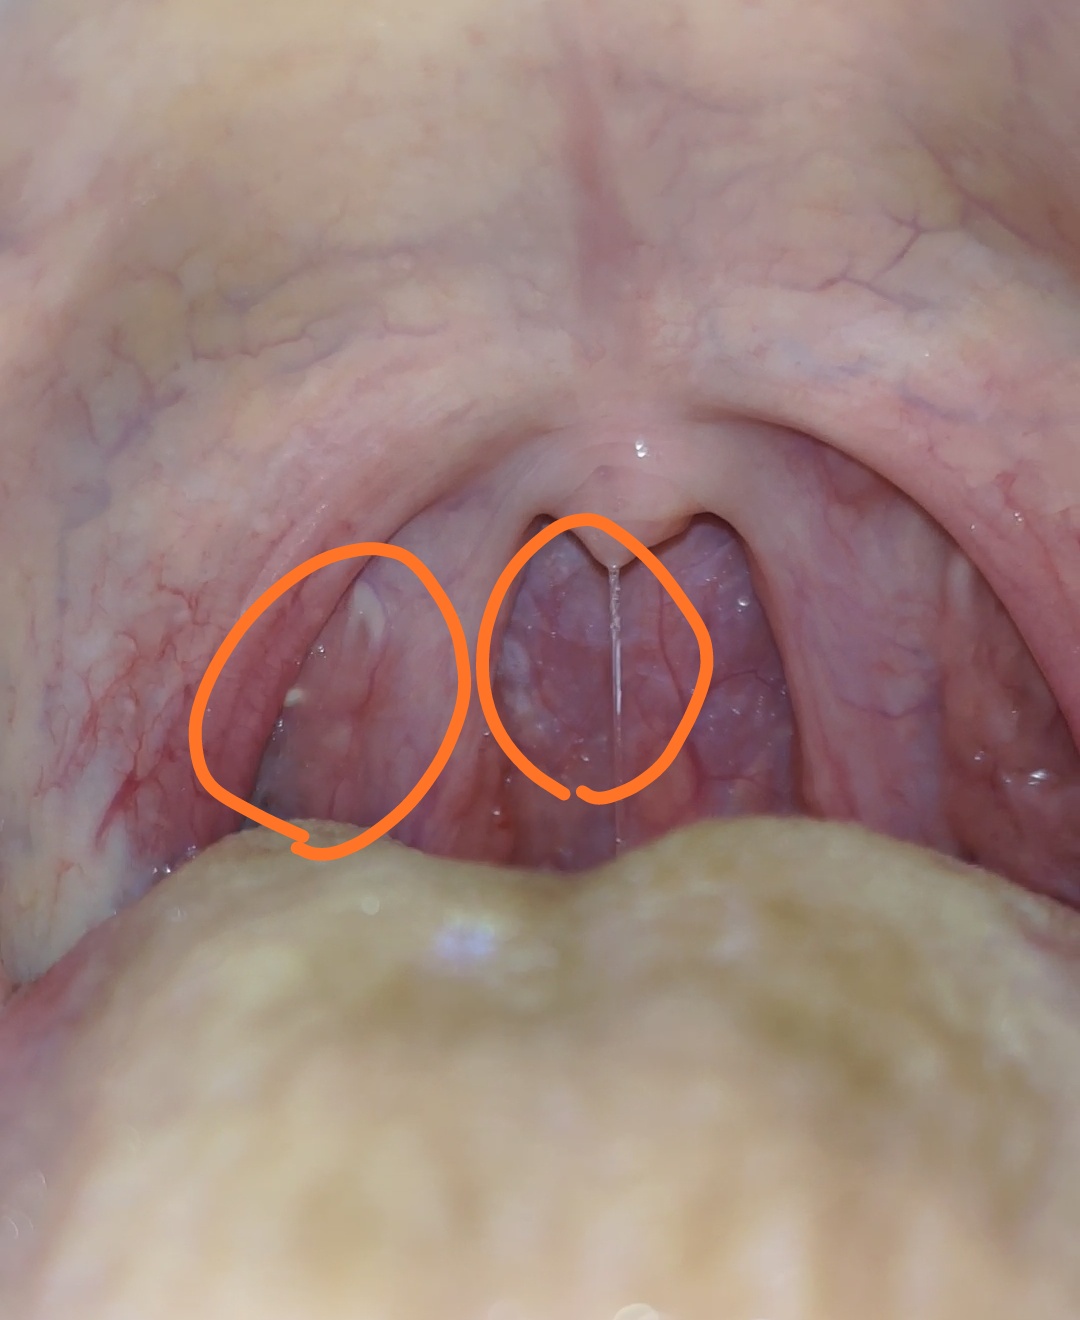

有异物感,燥热微疼,吃东西有能感觉到刮碰,每天还感觉到两边左右胸部有轻微疼痛,两个肩膀也有酸胀感,躺下后静下来就能敏感的感觉到燥热和异物感。一直在喝中药所以舌头很黄。

这个算扁桃体发炎吗?

滤泡咽炎加慢性扁桃体增生

真的吗?那个小疙瘩就是扁桃体增生吗?

真的吗?不过我已经有快两个月的不舒服感觉了,看了医生也说没事。刚开始的时候燥热感很严重,晚上睡不着觉。现在好多了。请问那个小豆豆是什么东西呢?

感觉像滤泡吧